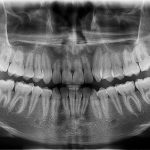

Panorámica de Maxilares

Es una técnica radiológica que muestra las estructuras óseas (los maxilares, la articulación de la mandíbula y los dientes) del rostro del paciente en una sola imagen general. Para ello, se vale de una máquina de rayos X especial, que rota alrededor de la cabeza del paciente.